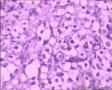

鼻腔新生物

性别年龄80临床诊断

一般病史鼻塞2月

标本名称活检

大体所见小组织3块,体积1*1*0.3cm

透明细胞病变,图片数量再多些,再清晰些,谢谢。这个年龄,肿瘤还是不能除外的。

良性,排除微生物感染

看不太清,考虑良性,重染

考虑良性病变。